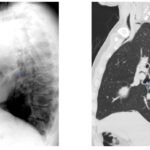

Dentro de los métodos diagnósticos, el neumomediastino se puede diagnosticar mediante radiografías o tomografía computada, donde se va a visualizar la presencia de aire (radiolucidez o hipodensidad lineales) rodeando las estructuras mediastinales. Un signo de muy alta especificidad es el llamado “signo del anillo alrededor de la arteria”, donde se visualiza una imagen radiolúcida o hipodensa en forma de anillo rodeando la arteria pulmonar, principalmente del lado derecho. Este signo ayuda a diferenciar esta entidad del neumopericardio, que puede verse similar en imágenes.

Among the diagnostic methods, pneumomediastinum can be diagnosed using X-rays or computed tomography scans, where the presence of air (linear radiolucency or hypodensity) surrounding the mediastinal structures will be visualized. A highly specific sign is the so-called “ring sign around the artery”, where a radiolucent or hypodense ring-shaped image is visualized surrounding the pulmonary artery, primarily on the right side. This sign helps differentiate this condition from pneumopericardium, which can appear similar on imaging.